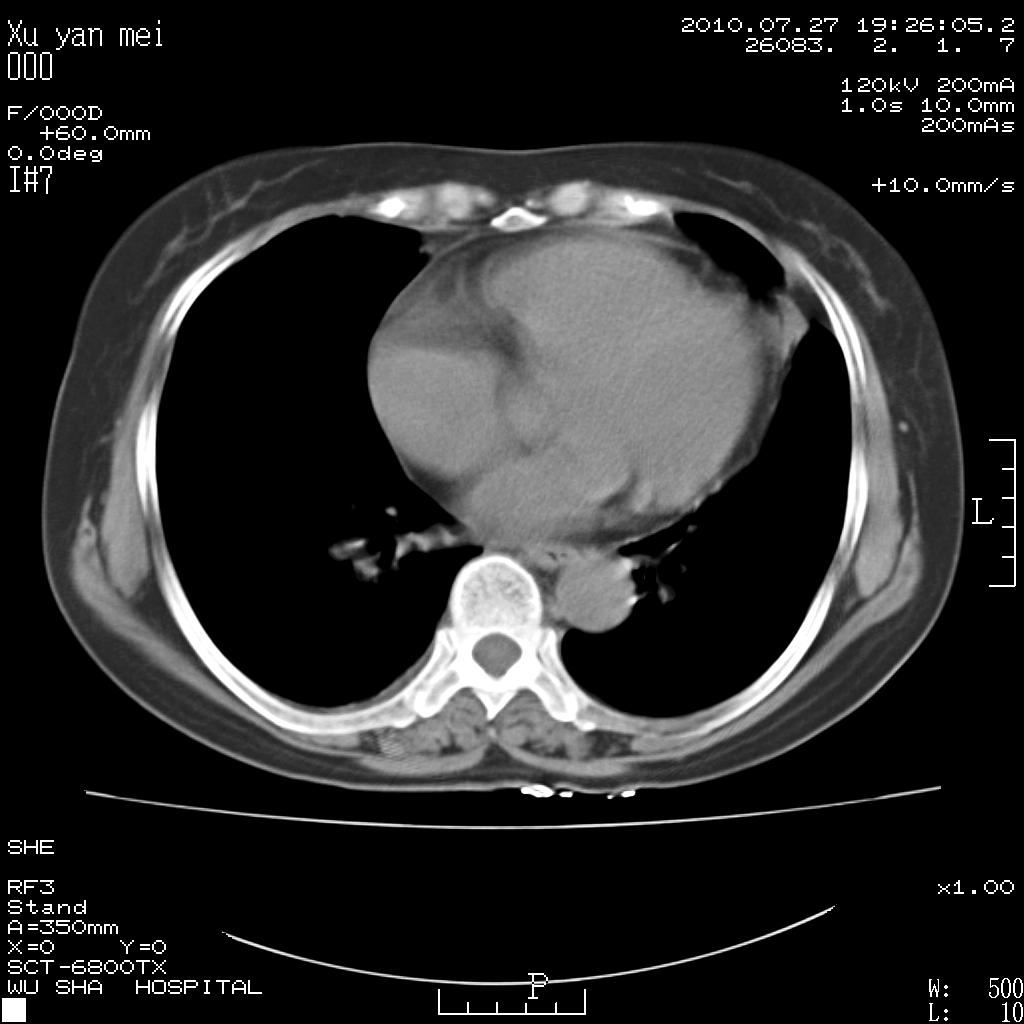

女,60岁,胸痛就诊,右肺结核?炎症?其它?(胸片右侧中上肺野确实看不到什么啊)

1)考虑两肺感染性病变;建议抗炎治疗后复查。2)双侧少量胸腔积液。

1)考虑两肺感染性病变;建议抗炎治疗后复查。2)右侧少量胸腔积液。

右侧少量胸腔积液,段性肺炎。

双肺炎症可能性大,建议抗炎后复查。右侧胸腔少量积液。双侧胸膜轻度增厚。

考虑两肺感染性病变;不除外肺栓;建议抗炎治疗后复查。